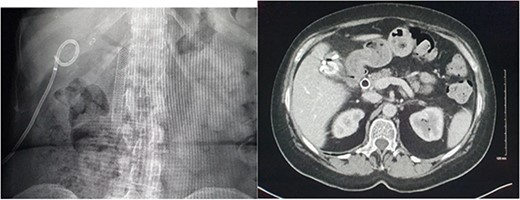

CT of the abdomen was performed the following week due to pyrexia and ongoing pain. This demonstrated abscess formation at the site of haematoma in the gallbladder fossa (Fig. 6). A locking pigtail drain was placed in the gallbladder fossa collection under ultrasound guidance. Slow drainage of bloodstained bilious fluid from the right upper quadrant with resolution was demonstrated on CT the following month (Fig. 7). The patient was discharged with gallbladder (GB) fossa drain and biliary stent in situ to await elective cholecystectomy.

Radiographic and CT images demonstrating the patients’ hardware at discharge with an endoscopic biliary stent and gallbladder fossa pigtail drain in situ.